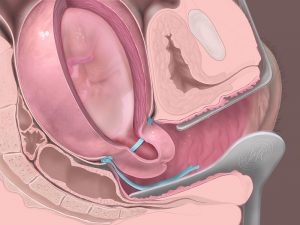

تلقیح داخل رحمی IUI (آی یو آی)

تلقیح داخل رحمی (IUI) کم تهاجمی ترین روش های کمک